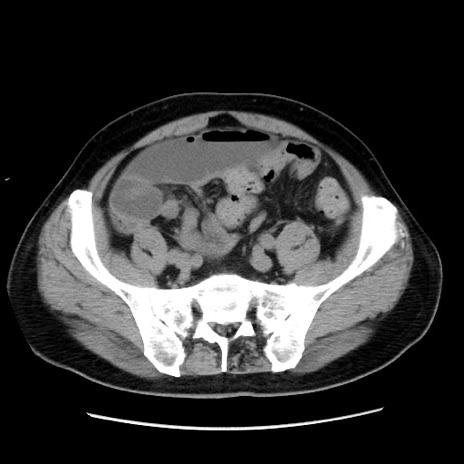

症例16(横断像)

【症例】 70歳代男性

【主訴】 腹痛、嘔吐

【現病歴】 約1ヶ月前より間欠的に腹痛と嘔吐あり、当院消化器内科を受診したところCTで多発する肝臓のLDAを指摘され、精査中であった。以降は消化器症状は安定していたが、2日前より嘔気と腹痛があり、同日より排便・排ガスが消失した。改善認めず、 本日、救急外来を受診した。

【既往歴】 大腸ポリープ切除後。

【身体所見】意識清明・会話良好、BT 36.3℃、BP 127/80mmHg、 P 80bpm、腹部:膨満あり、平坦・軟、上腹部正中および下腹部正中に圧痛あり、反跳痛なし、筋性防御なし。

【データ】WBC 7200、CRP 0.77